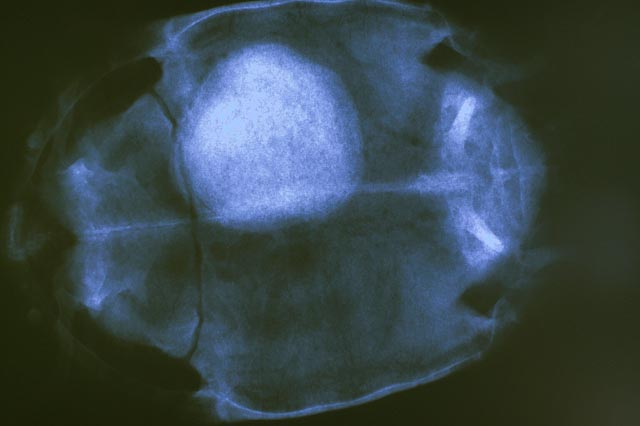

在这种环境中可能导致的后果如下图:

没错,这就是结石,触目惊心!